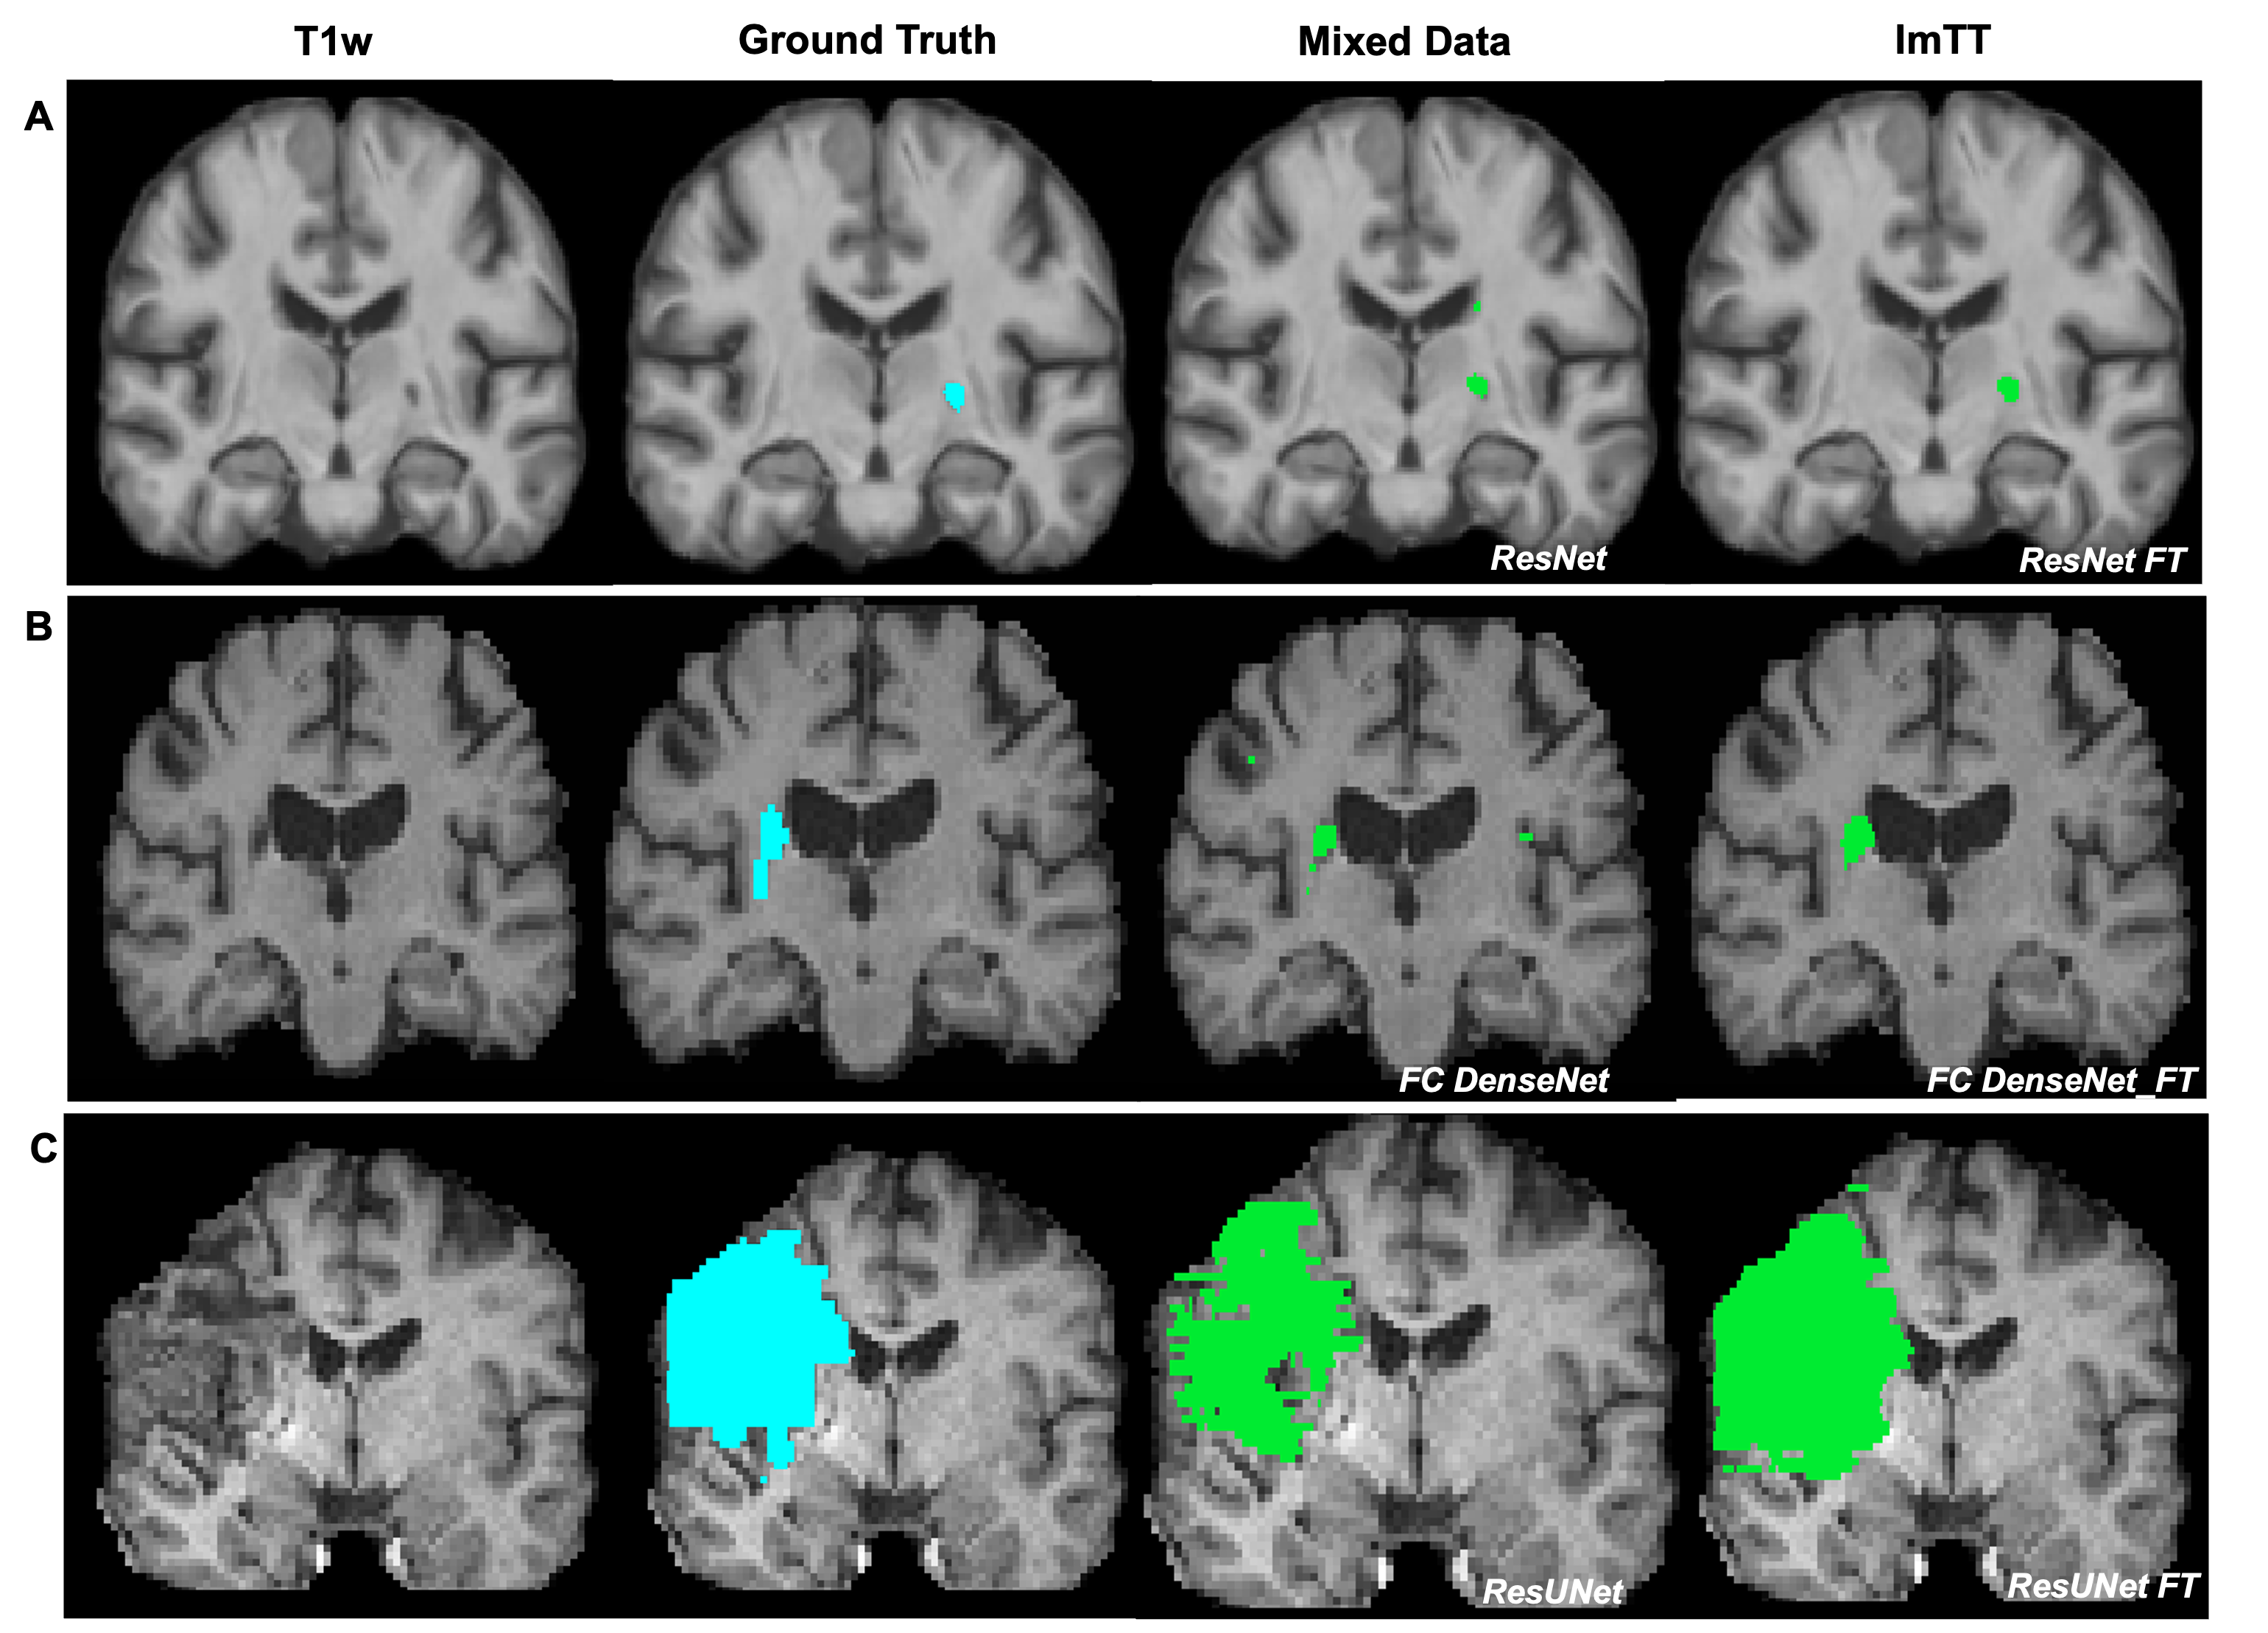

Figure 4: Comparison of hand-drawn lesion maps and lesion map predictions from two distinct model training approaches. A, B, C display predictions from ResNet, FC DenseNet, and ResUNet (trained with mixed data) alongside ResNet_FT, FC DenseNet_FT, and ResUNet_FT (trained using ImTT) respectively.

3.4 Visual comparison

Figure 4 presents a comparative analysis of prediction results from two distinct training approaches for models, as discussed in Section 2.4. A, B, C shows three separate predictions generated by three different model architectures on brain MR images in the independent validation set. It is evident that the mixed data approach leads to some false positives in the models’ predictions, which are effectively eliminated when employing the ImTT training approach.